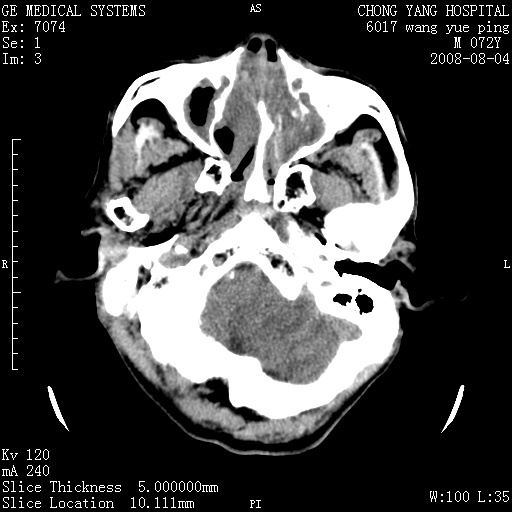

标题: CT14987:M72Y,头痛头昏,BP220/110. [打印本页]

标题: CT14987:M72Y,头痛头昏,BP220/110.

1)考虑左侧小脑脑梗塞。2)脑白质病。3)脑萎缩。4)双侧鼻腔新生物(息肉?)并阻塞性副鼻窦炎。

1.左侧小脑大面积梗塞;2.左侧基底节区腔梗;3.白质疏松;4.脑萎缩;5.慢性副鼻窦炎

小脑左侧病灶呈扇形分布,增强后未见明显瘤体样节结影,病变区未见强化。

支持:左侧小脑脑梗塞梗塞表现

另:脑白质病。脑萎缩。双侧鼻腔新生物(息肉?)并阻塞性副鼻窦炎。

1)考虑左侧小脑脑梗塞,建议治疗后复查除外其他,左基底节区腔隙性脑梗塞2)脑白质变性3)脑萎缩。4)双侧鼻腔新生物(息肉?)并阻塞性副鼻窦炎。